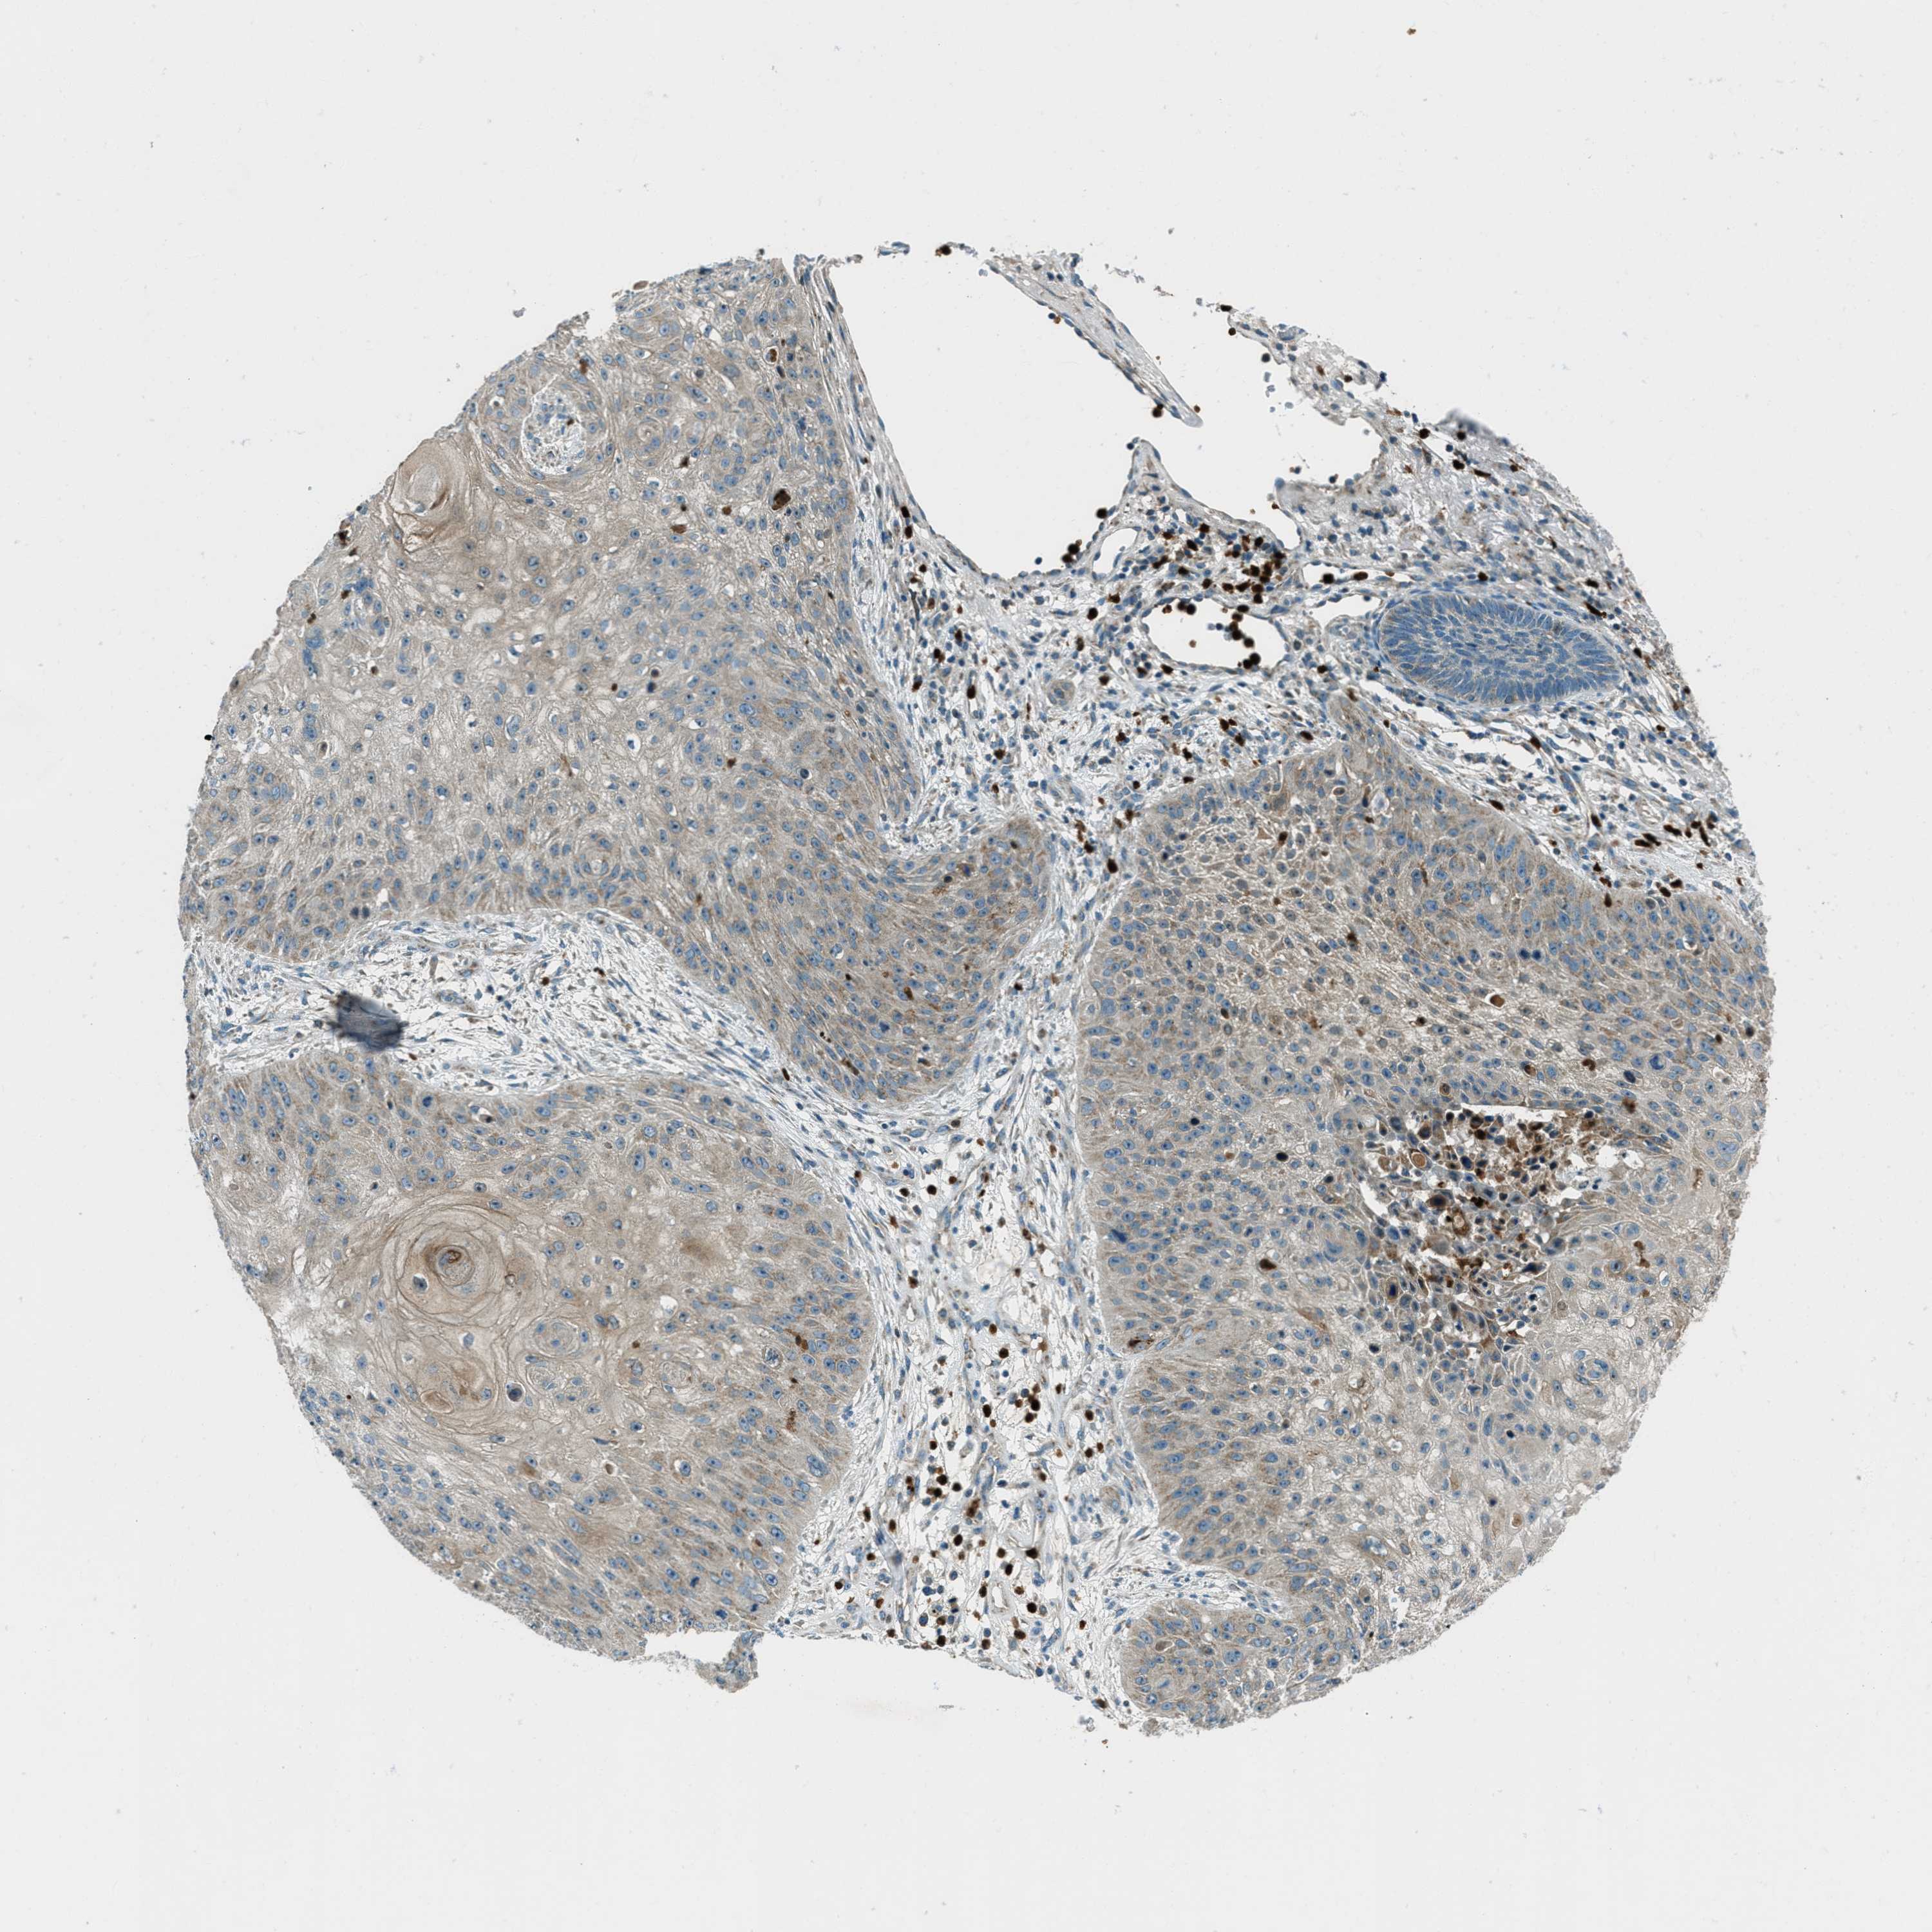

SKIN CANCER - Protein expressioni

A mouse-over function shows sample information and annotation data. Click on an image to view it in a full screen mode. Samples can be filtered based on level of antibody staining by selecting one or several of the following categories: high, medium, low and not detected. The assay and annotation is described here.

Antibody stainingi

Antibody staining in the annotated cell types in the current human tissue is reported as not detected, low, medium, or high, based on conventional immunohistochemistry profiling in selected tissues. This score is based on the combination of the staining intensity and fraction of stained cells.

Each image is clickable and will lead to virtual microscopy that enables deeper exploration of all samples and also displays staining intensity scores, fraction scores and subcellular localization as well as patient and tissue information for each sample.

Antibody HPA017322

Staining

High

Medium

Low

Not detected

Intensity

Strong

Moderate

Weak

Negative

Quantity

>75%

75%-25%

<25%

None

Location

Nuclear

Cytoplasmic/membranous

Cytoplasmic/membranous,nuclear

Squamous cell carcinoma in situ, NOS

Squamous cell carcinoma, NOS

Squamous cell carcinoma, metastatic, NOS

Basal cell carcinoma